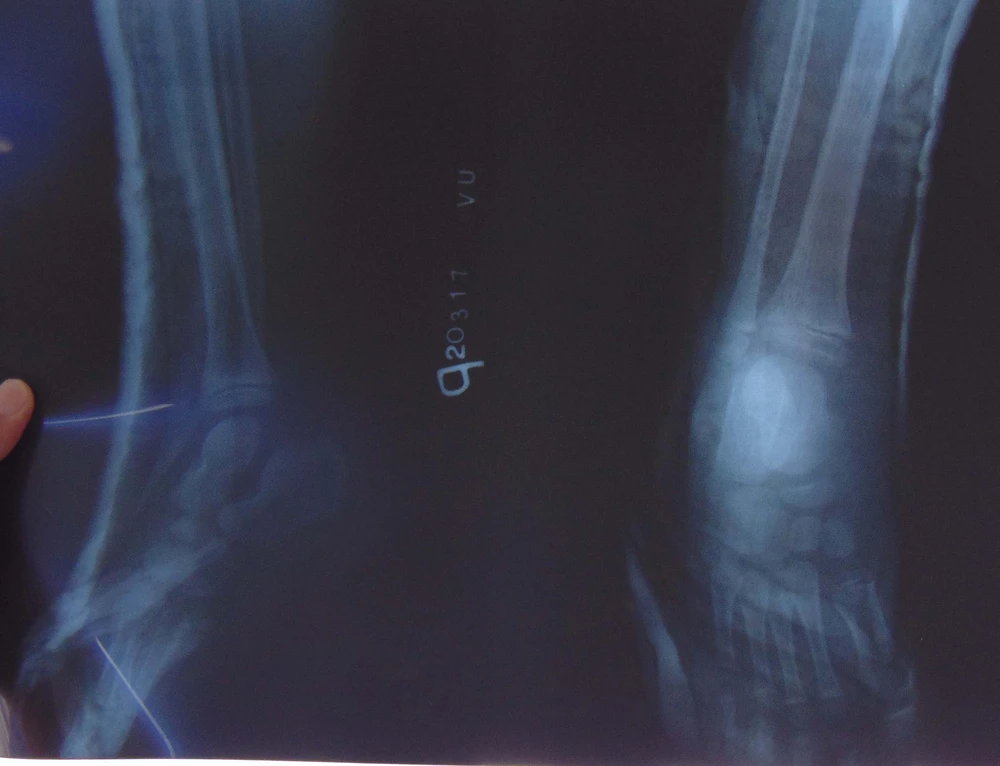

Kết quả chụp X-quang cho thấy gót chân phải bệnh nhi bị gãy. Ảnh: TRẦN NGỌC

Sau khi thăm khám và chụp X-quang, kết quả chụp X-quang cho thấy gót chân phải của bệnh nhi bị gãy. Sau đó, các BS đã rửa sạch, khâu kín phần da bị rách rồi nẹp và băng bột gót chân.